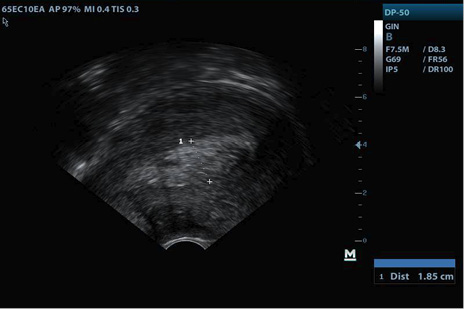

Consultó al médico ginecólogo en consulta privada, cuatro días después de la expulsión del producto, manifestando escaso sangrado y leve dolor pélvico; a su ingreso se encontró paciente tranquila, afebril, sin taquicardia ni taquipnea, abdomen blando, al examen con espéculo cérvix cerrado, escaso material sanguinolento en vagina, sin mal olor; en la ecografía se observó, como hallazgo positivo, endometrio irregular de predominio homogéneo con algunas zonas hipoecoicas, de 18,5 mm en corte longitudinal (Figura 1). Se ordenó cuadro hemático, GCH cuantitativa, evitar coitos y tactos vaginales, y se instruyó en signos de alarma.